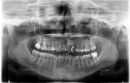

Очень сильно разболелся передний нижний зуб. Через какое-то время (4-5 часов) стала болеть сильно вся нижняя челюсть. Сегодня обратилась к стоматологу, отправили на снимок. Врач сказал, что воспалены все нервы передних зубов и их необходимо лечить, но прежде пропить антибиотики. Местным врачам не доверяю, нахожусь в командировке. Терплю до приезда.

По данному снимку не видно воспаления на всех передних зубах, депульпировать их все не нужно. Желательно сделать прицельные рентгеновские снимки этих зубов и провести осмотр, выявив причинный зуб.

Проконсультируйтесь с другим специалистом. Вместо антибиотика лучше пропить курс нестероидных противовоспалительных препаратов (5 дней, согласно инструкции и отсутствия противопоказаний).